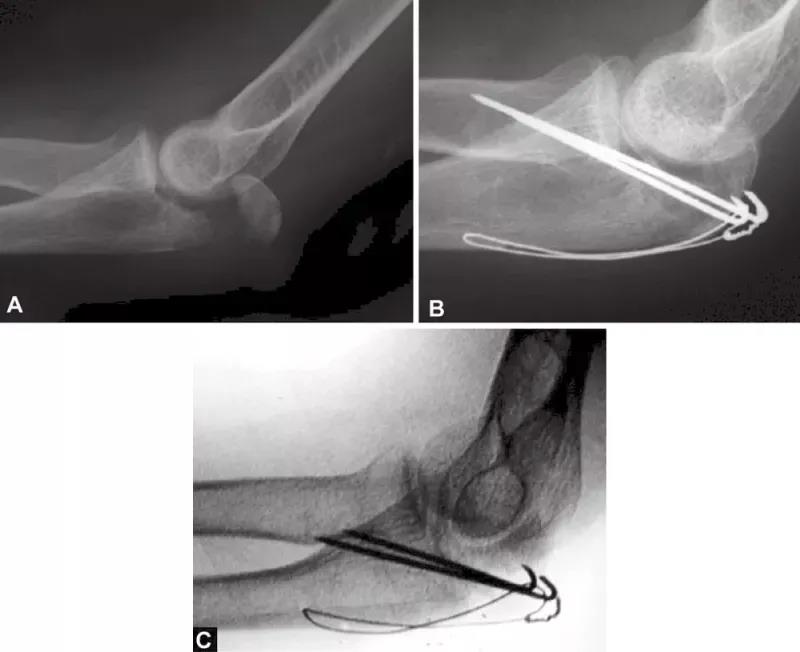

图3A~C关节压缩骨折在鹰嘴斜位片中完全隐匿。在箭头的部位变窄可能是一个提示。如果不知道这种可能性,医生就会忽略该手术X线片检查中明显的关节面压缩骨折。术后标准的侧位片良好地显示了关节面压缩骨折。该医生未能完成最初的手术目标